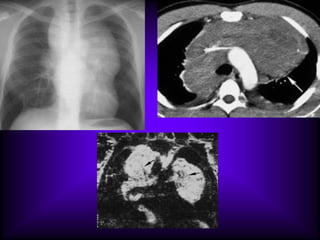

Pneumatocele is a benign air containing cyst of lung, with

thin wall < 1mm as bulla but with different mechanism 

Infection with staph aureus is the commonest cause ( less

common causes are, trauma, barotrauma) lead to necrosis

and liquefaction followed by air leak and subpleural

dissection forming a thin walled cyst.